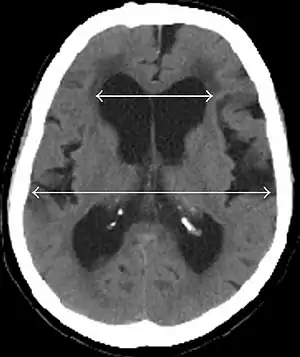

| Evan's index is the ratio of maximum width of the frontal horns to the maximum width of the inner table of the cranium. An Evan's index more than 0.31 indicates hydrocephalus.[2] | |